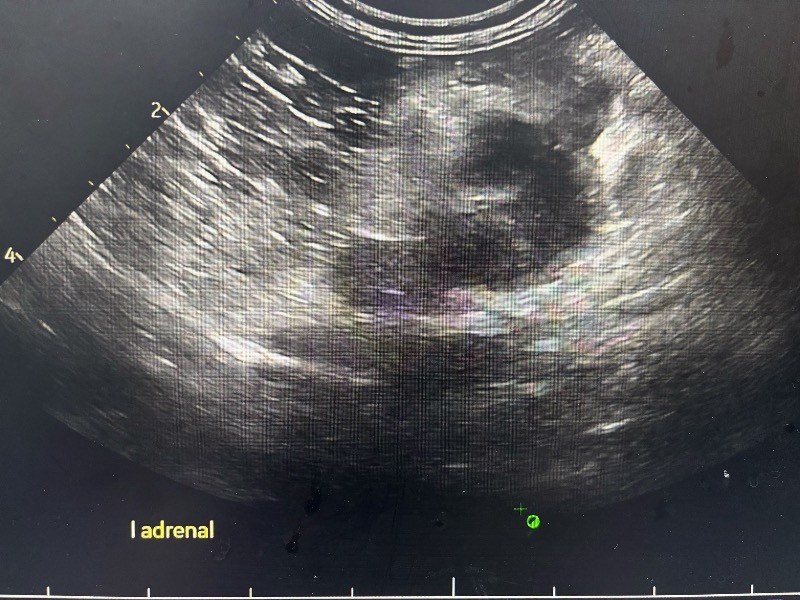

妍兒 2025-09-29 她剛開完拆膽䉴手術 跟拆脾藏 過了五天出院⋯ 愛犬睡到凌晨三點走了 請問是腎上腺腫瘤破裂造成休克嗎? 他的醫生是這樣說!還說腫瘤不能開刀她13歲了 、還有腫瘤位置也不能開刀旁邊有大血管! 真的好難過 懇請有醫生知道能跟我說ㄧ下 腎上腺腫瘤破裂真的會造成死亡嗎? 姚勝隆 院長 2025-10-07 治療中或術後的動物,建議與主治獸醫師多討論,只有主治獸醫師最清楚寵物的病況。 1 分享–– 我也要提問